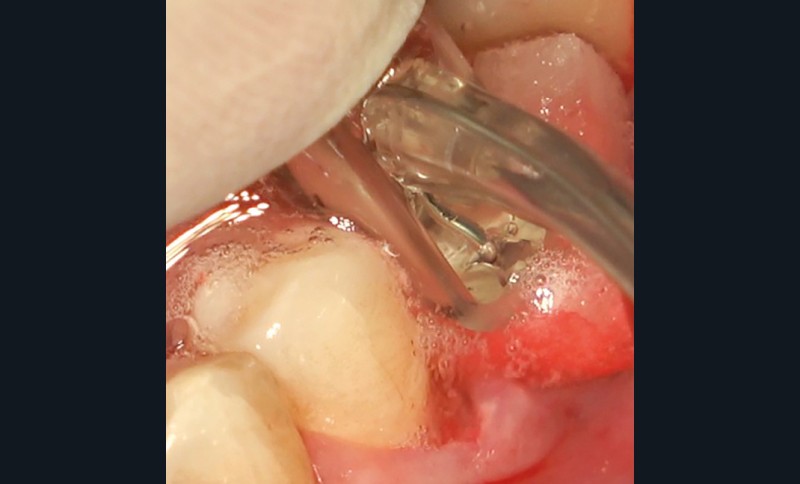

- Péri-implantite diagnostiquée en 2021

Chez ce patient, le traitement de la péri-implantite a comporté une chirurgie associant décontamination électrolytique de la surface implantaire, régénération osseuse guidée et enfouissement de l’implant. Le résultat à 2 ans est très moyen au vu du pourcentage de régénération osseuse obtenu. Comment peut-on prévoir un tel résultat alors que l’on a suivi les recommandations à la lettre, que l’on a utilisé les dernières technologies de décontamination, que l’on y a mis tous les moyens, que le patient est en bonne santé générale et qu’il vient en plus régulièrement aux séances de thérapeutique de soutien ? Le succès du traitement des péri-implantites n’est pas simple à obtenir, surtout quand un élément clé est compromis… la maintenance personnelle ! En effet le succès n’est possible que si le contrôle de plaque quotidien est optimal et, ici, ça n’était pas le cas. Le patient se brossait certes les dents, mais ne passait pas quotidiennement les brossettes, ce qui…